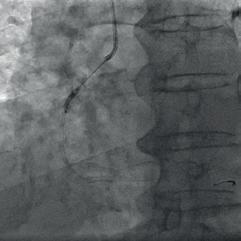

The patient was admitted to the intensive care unit with findings consistent with a diagnosis of NSTEMI. The onset of symptoms was one day prior. Previous medical history included arterial hypertension, dyslipidaemia and positive family history of cardiovascular disease. The electrocardiogram performed on admission was unremarkable except for the presence of a Q wave and a negative T wave in lead III. Laboratory tests revealed an elevated level of high-sensitivity troponin level (938, reference range 0 – 14 ng/L). Invasive coronary angiography revealed two-vessel disease with borderline (50 – 60 %) stenosis of the mid-LAD and a severely calcified, totally occluded right coronary artery (RCA) (Fig. 1).

Figure 1: Initial appearance of the RCA in the LAO view. Figure 2a: RCA dilatation with